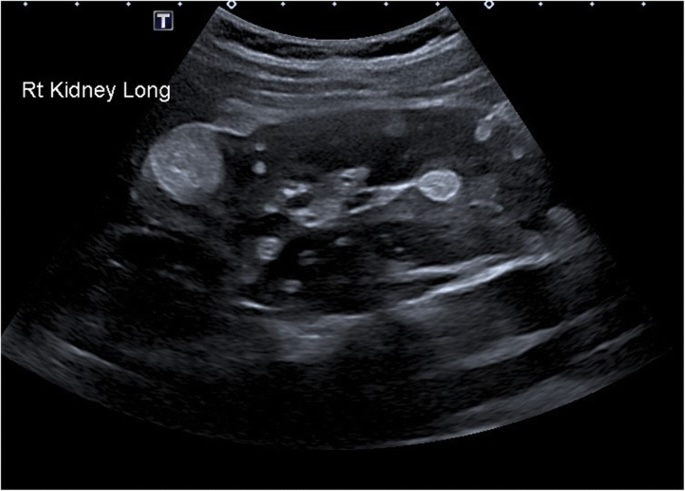

Ультразвуковое исследование при туберозном склерозе проводится в В-режиме с допплерографией органов брюшной полости, почек, сердца и щитовидной железы. Цель обследования — выявление ангиомиолипом, фибром, кистозных и солидных образований, характерных для системного поражения внутренних органов при этом заболевании.

Ультразвуковое исследование выявляет следующие анатомические признаки туберозного склероза:

Множественные ангиомиолипомы почек, представленные гиперэхогенными гомогенными образованиями овальной или дольчатой формы без акустической тени.

Кисты паренхимы почек различных размеров, с анэхогенным содержимым и чёткими контурами.

- Надёжная идентификация ангиомиолипом почек по характерной эхогенности и однородности структуры.

- Выявление сопутствующих кистозных изменений в почках и печени с оценкой размеров и капсулы.